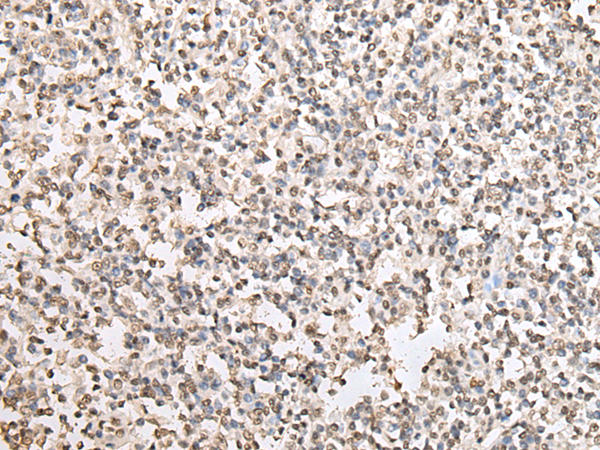

分类: 科研抗体货号: P05811别名: RN49018应用: IHC反应种属: Human, Mouse